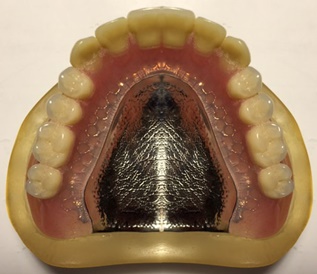

●金属床の総義歯(自費)

プラスチック系の材料とコバルトクロームやチタン等の金属からできている入れ歯です。

フレームの部分が金属なので非常に薄く仕上げることができ、使用していて違和感が少なく発音もしやすい。食べ物の温かさや冷たさに対する感覚も自然に近い。精密にできているので吸着(顎への吸い付き)がよく、外れにくい。壊れにくく長持ちである。治療費に関して選定療養費制度を利用できます。